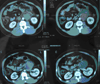

Case presentation: A case of burned-out tumor of the testis in a 31-year-old man is reported. The tumor presented as a retroperitoneal mass with histological characteristic of a seminoma. The testes on clinical examination were normal, and a suspicious lesion in the scrotum was only identified after ultrasound. Incision of the abdominal mass was decided, followed by orchectomy. Histological examination of the testis revealed a suspicious lesion with characteristics of spontaneous regression of germ cell tumors.